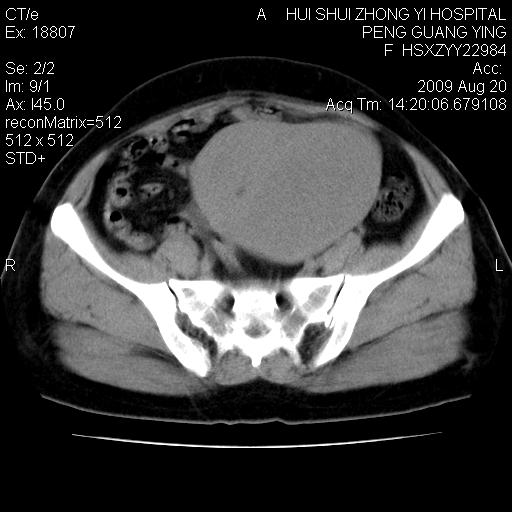

标题: CT21707:女,42岁,因发现下腹部包块2月。 [打印本页]

标题: CT21707:女,42岁,因发现下腹部包块2月。

增强看看,倾向于子宫肌瘤并囊变或腺肌征,宫腔少量积液。

病灶来源——子宫?附件?

从平扫角度看本人还是倾向于子宫肌瘤诊断,宫腔少量积液。

目前的影像表现显示肿块位于腹腔及盆腔,但具体定位,分清来源较困难,是否来源于卵巢、子宫无法定论,子宫直肠及子宫膀胱周围脂肪间隙尚较清晰,如果患者有过腹腔好或者盆腔手术史,也可以形成不典型的血中,最好手术后定为定性,我期待结果。

软组织密度,与子宫一致。双侧卵巢形态、密度好,不支持来源于卵巢。